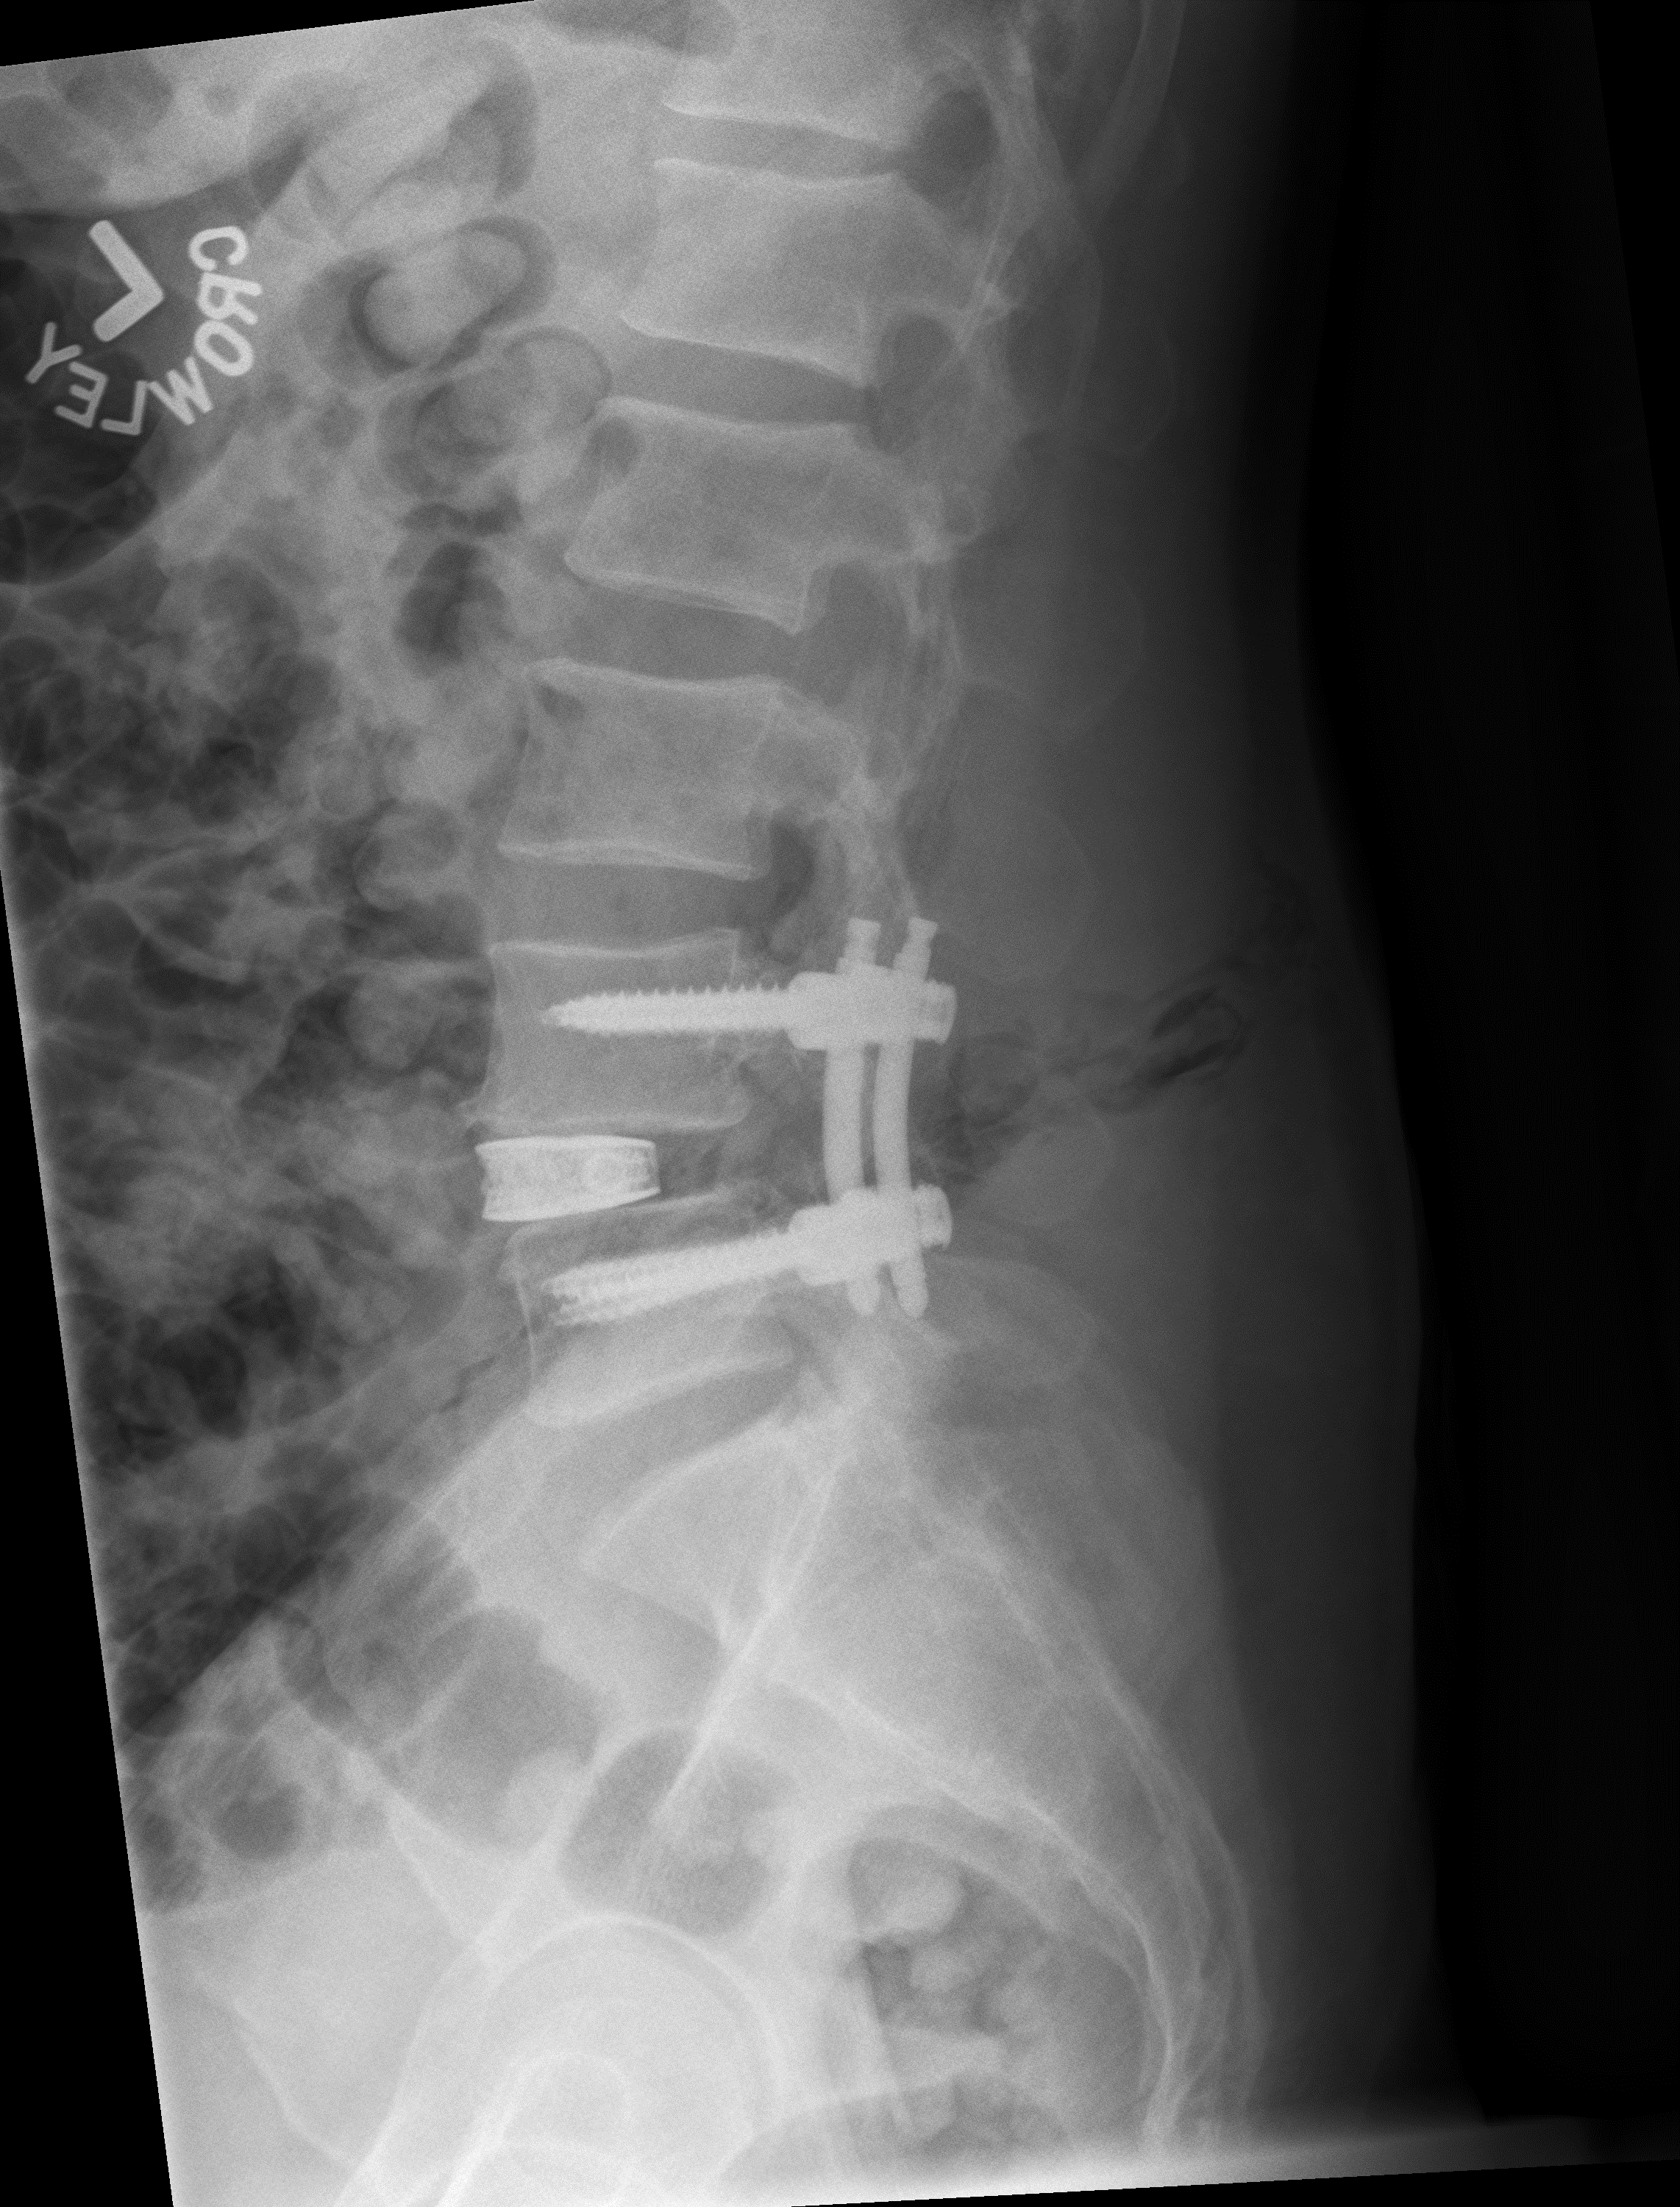

This minimally invasive procedure only requires a small incision on the patient’s side, hence the word “lateral” in the name, as well as one or two small incisions on the back. From there, Bennett uses imaging and nerve monitors to guide his surgical instruments to reach the lower spine, or lumbar. At that point, he removes the diseased disc and replaces it with a titanium spacer implant to help improve the alignment of the spine and to take pressure off any nerves that have been pinched.

He then places screws and rods through small poke holes in the back to provide additional strength and stability without compromising the patient’s low back muscle.

Technology in the spacer is used to help stimulate bone growth so that the connecting bones in the spine will grow into and through the implant, making the spine strong and stable. The procedure takes about 90 minutes and most insurance companies cover it.

The procedure was successfully completed in August 2019 at Novant Health Forsyth Medical Center. Bennett says that this procedure is not for everyone, but that it was an excellent option in this case.